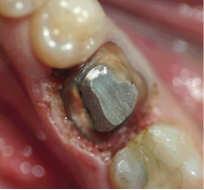

Surgery with Laser since the prosthetic edge

At this treatment and setting, one work with Anestesie. The anaemic working, allow us a very good view to be able to prepare a perfect tooth stump.

In one single treatment, the gingivectomy can done and the tooth stump is prepared.